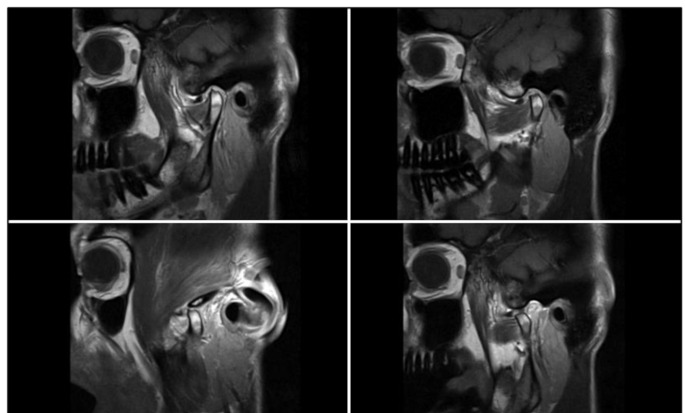

Methods: Non-experts for the purposes of this study were recruited from German dental students. After a focused instruction on TMDs, they completed two evaluation rounds to identify and assess selected pathologies of arthrogenic TMDs in patient cases. Initially, participants were provided with MRI images only; in a second round, additional arthroscopic video material was provided. Statistical analysis was performed to evaluate responses, and inter-rater reliability among non-experts was determined.

Results: 94 participants evaluated a total of 30 MRI scans of the temporomandibular joint (TMJ) obtained from 27 patients who had also undergone arthroscopy. Their assessment showed the relatively highest agreement with the correct diagnosis for disc perforations (68.2-71.9%) and when using both MRI and arthroscopy material. Synovitis showed the lowest agreement, and was more successfully detected based on arthroscopy (47.2%) alone. Overall, there was only slight to fair agreement among the study participants across diagnoses (Kappa 0.074-0.358). Non-experts showed significant inconsistencies in interpreting MRI and arthroscopic imaging, with only limited concordance with the actual diagnosis and an agreement rate of less than 71.9%.